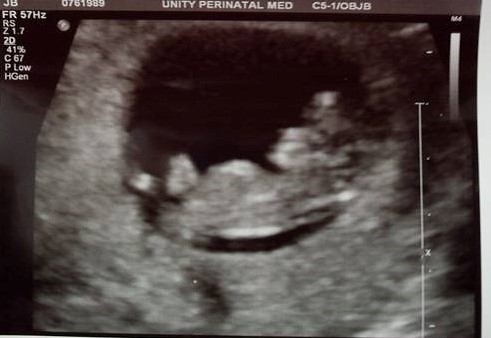

Finally! Met our rainbow baby yesterday, measuring spot on at 10w+1 and heartbeat at about 150/min. LO had the sweetest hiccups that we could see on the u/s, I'm in love!